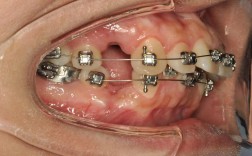

带环佩戴的注意事项

- 隔湿与粘接:佩戴前需严格隔湿(用棉球隔湿或橡皮障),避免唾液污染影响粘接;粘接剂常用玻璃离子水门汀或树脂,需按产品说明操作,确保带环与牙面紧密贴合。

- 边缘处理:带环边缘应位于牙龈缘上方0.5-1mm,避免压迫牙龈导致炎症;若边缘过深,需用牙龈分离器推开牙龈或重新选择型号。

- 咬合调整:佩戴后需检查咬合关系,避免带环过高导致早接触(用咬合纸标记,磨除高点)。